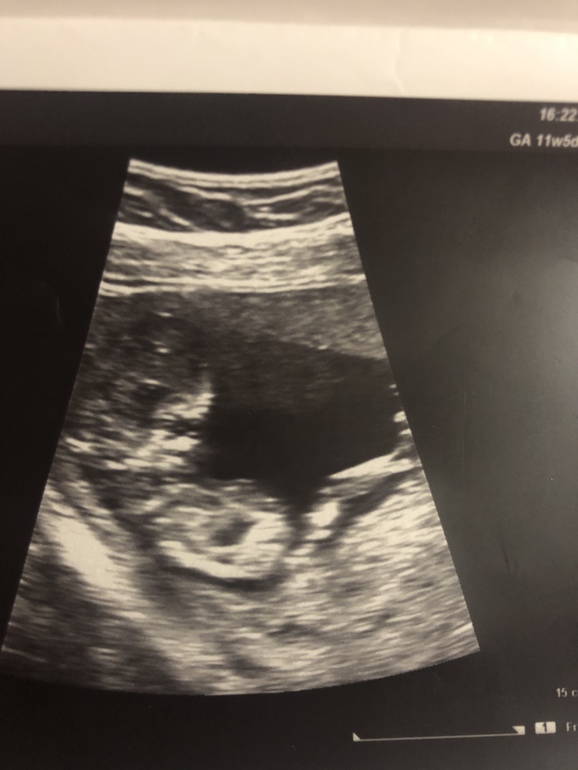

Мальчишка/ девчонка ?)

ТонусСегодня была на узи внепланово, так как потягивал пару дней живот, насмотрели небольшой тонус..

Я была удивлена как мы выросли 🤗🤗🤗

Последний раз была на узи в 6 недель, только точку увидела, а тут целый человек!)

11 недель и 6 дней срок

Не могу понять : на второй фото это половой бугорок или пуповина? Потому что на первой ничего не торчит ))